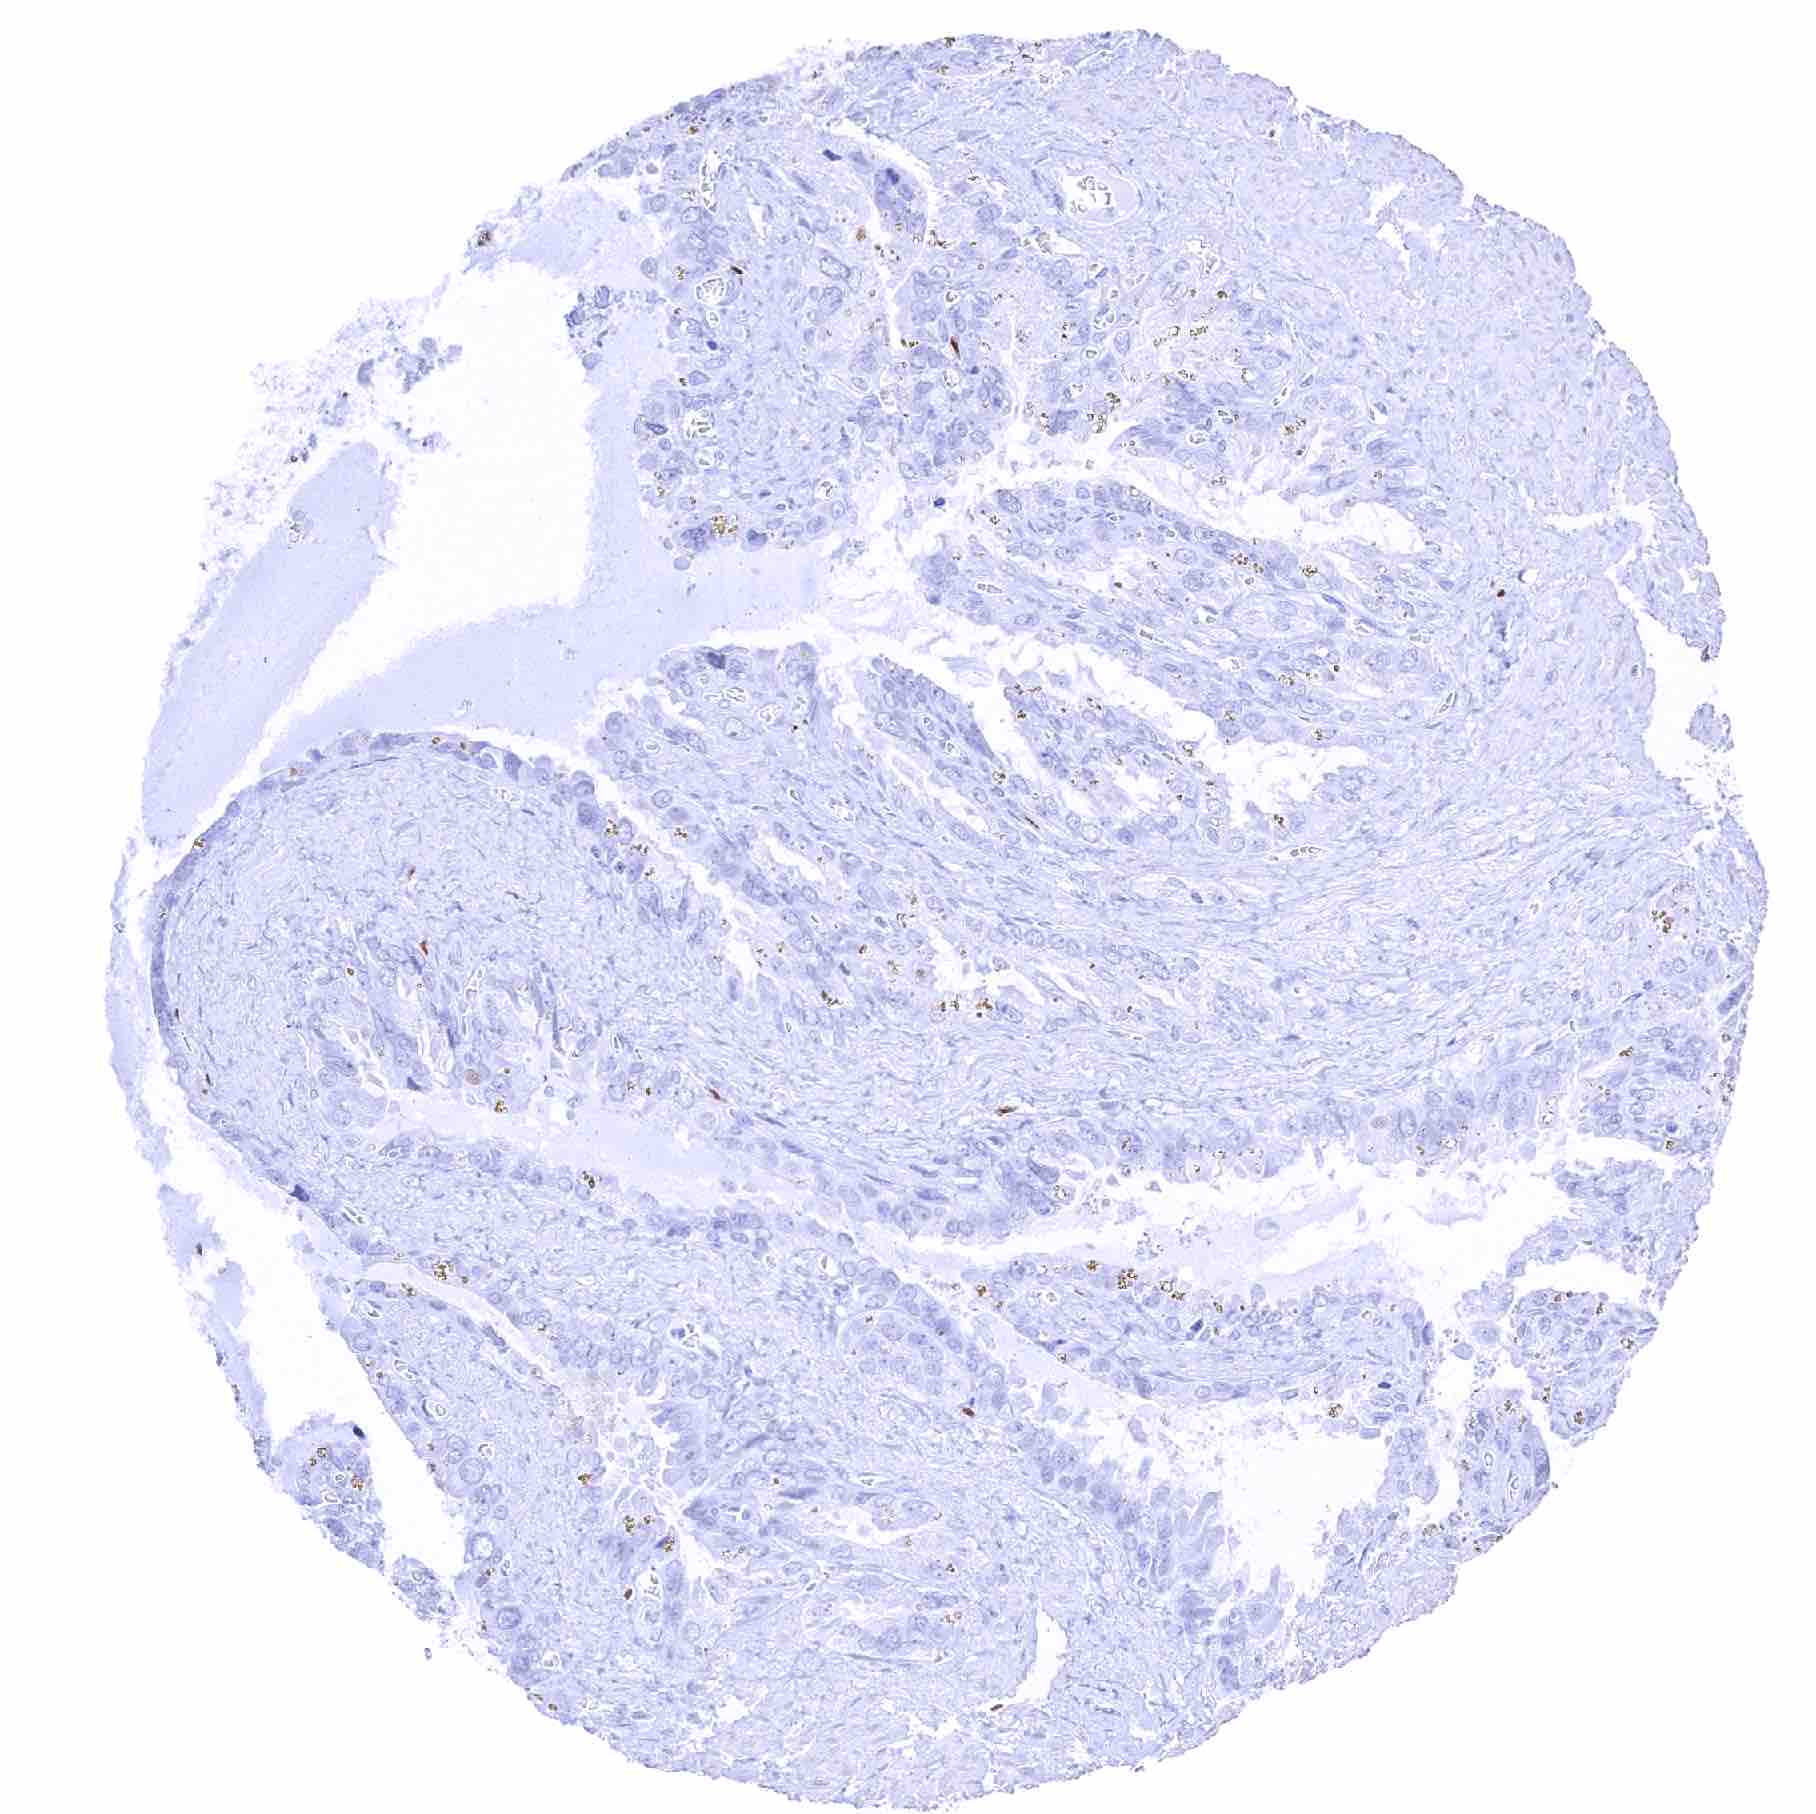

Stomach, antrum – Significant SOX2 staining of a fraction of glandular cells

Stomach, antrum